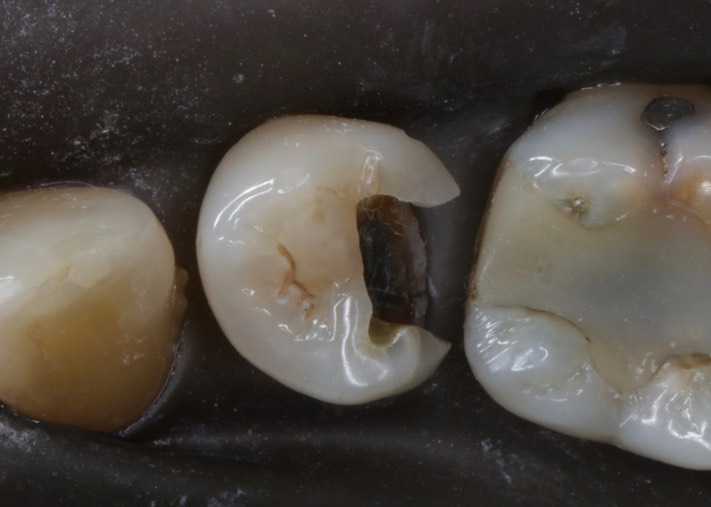

Brian Sato #20 amalgam removal